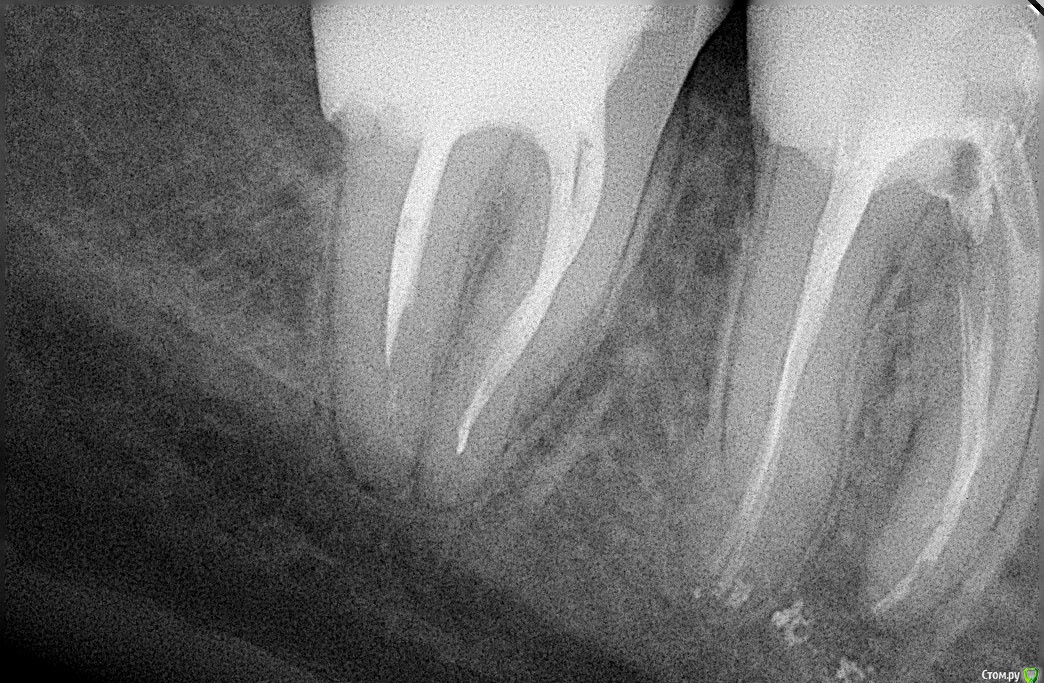

Didi Опубликовано 30 декабря, 2016 Поделиться Опубликовано 30 декабря, 2016 (изменено) После пломбировки 6-го зуба снизу он болел при накусывании один или два месяца.Спустя 6 лет после пломбировки, после регулярной чистки между зубами толстой нитью (раньше там не чистил), на следующий день этот зуб начал снова болеть при накусывании и шатании. Как только прекращаю чистить между зубами толстой нитью, боль при накусывании проходит через 2-3 дня. Наверное происходит давление на зуб при вытаскивании нити, из за которого он начинает болеть на следующий день. В других зубах с запломбироваными каналами после чистки между ними болей нет. Другие зубы в отличии от этого после пломбировки болели максимум неделю.В болящем зубе есть стекловолоконный штифт. (может дело в нём?)Зуб запломбирован жидкой гуттаперчей B-sustem.Пломбировала стоматолог женщина. На снимках болит зуб тот что справа. Посмотрите пожалуйста прямо сейчас.ВопросНормально ли то что зуб болел после пломбировки 1-2 месяца, а спустя 6 лет начинает болеть после чистки толстой нитю между зубами, на следующий день? Если нет то в чём скорей всего причина и что делать?Буду благодарен Вам за помощь Изменено 30 декабря, 2016 пользователем Didi Ссылка на комментарий

Гарриевич Опубликовано 5 января, 2017 Поделиться Опубликовано 5 января, 2017 вам нужно рациональное протезирование этого участка и в целом. Если хотите более достоверной информации о состоянии этих зубов, то сделайте Кт Ссылка на комментарий

St. Опубликовано 6 января, 2017 Поделиться Опубликовано 6 января, 2017 (изменено) А если после пломбировки зуб при накусывании болит месяц и больше, то о чём это скорей всего сигнализирует?Причины могут быть разными, нужно разбираться в каждом конкретном случае что было до, что делали, что получилось после пломбировки, есть ли какая-то динамика со временем, какая ситуация с соседними зубами, с организмом вцелом и т.п. Потому что боль бывает от объективных каких-то причин(не то лечили, не так, перестарались при пломбировке, пропустили трещину корня), а бывает индивидуальная необъяснимая реакция на вмешательство (когда вроде бы все сделано хорошо и правильно, а все равно болит). В таких спорных ситуациях нужен очный осмотр и КТ. Изменено 6 января, 2017 пользователем St. Ссылка на комментарий